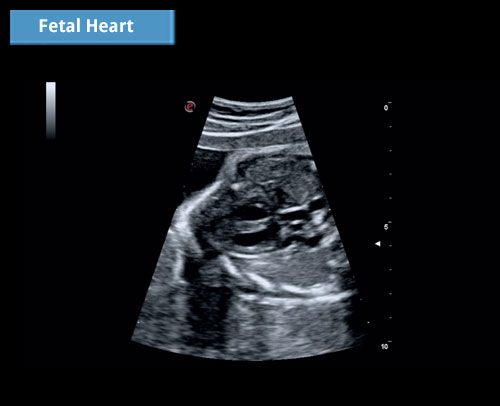

Fetální kardiologie: Zobrazování s vysokým rozlišením schopné vizualizovat jakékoli konkrétní detaily.